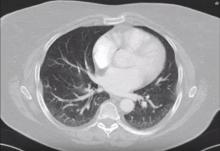

A 65-year-old female patient was admitted to the author’s clinic for the treatment of a predominantly lepidic adenocarcinoma located in the superior segment of the right lower lobe. Due to the ideal location and size, anatomical segment resection and radical lymphadenectomy was planned.

A fissure-last, video-assisted thoracoscopic (VATS) resection of the superior segment of the right lower lobe was performed using a 3 cm uniportal posterior approach, and was followed by a mediastinal lymphadenectomy. The frozen section analysis revealed microscopic presence of lepidic tumor on the resection margin, so a completion lower lobectomy was performed. The postoperative course was event free and the patient was discharged on the fourth postoperative day. The 1.8 cm diameter tumor was diagnosed as a primary lepidic (80%) and acinar (20%) adenocarcinoma staged pT2aN0M0.